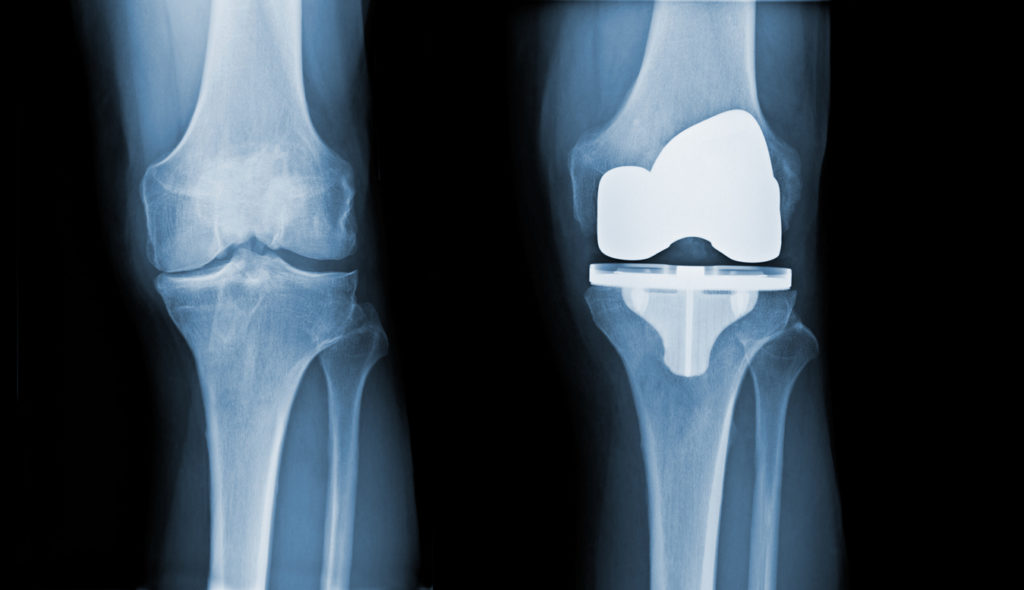

Total knee replacement replaces damaged joint components with smooth and durable synthetic parts. Though highly successful, this surgery requires time, effort, and a detailed post-operative plan.